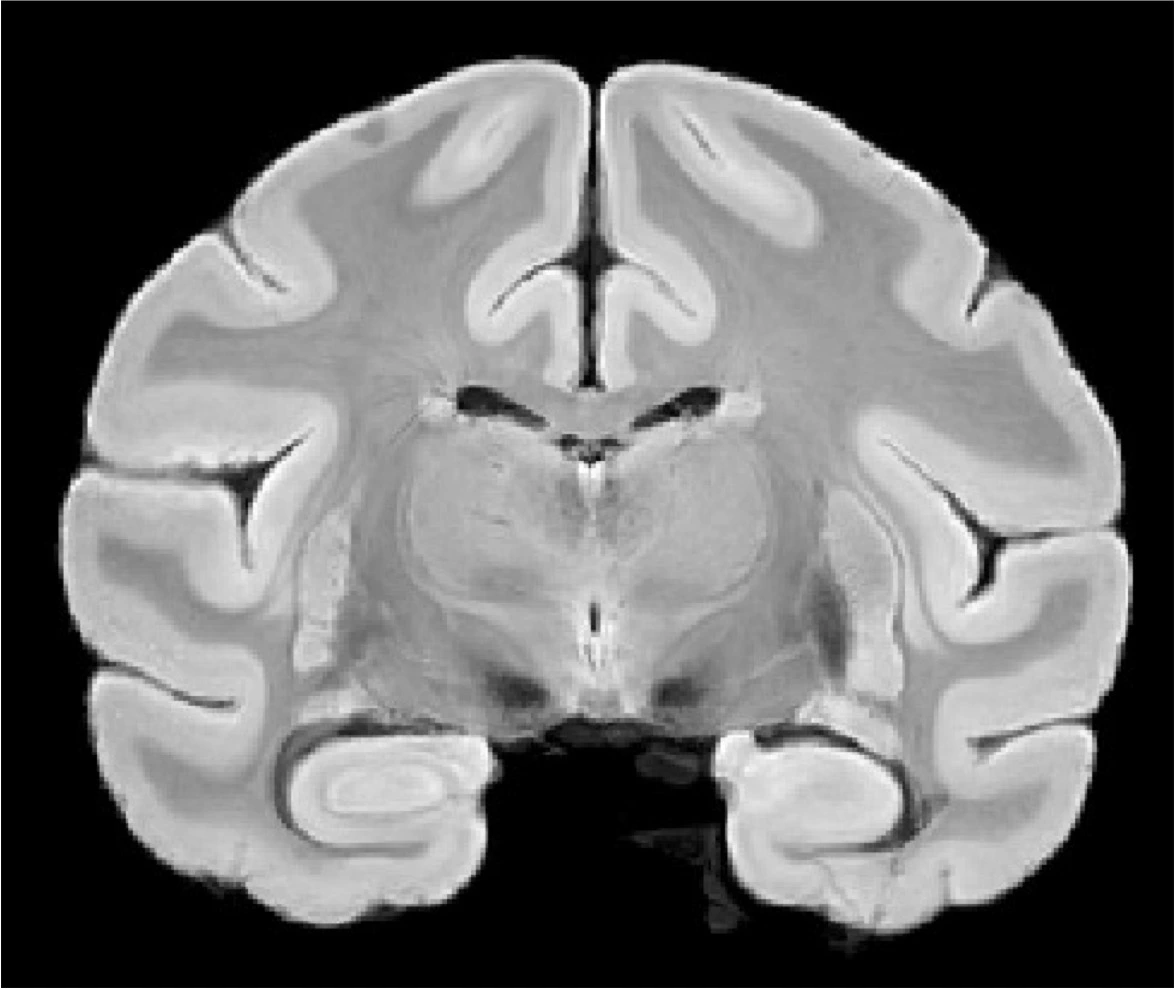

Bonnet Macaque High-Resolution Anatomical MRI (Laurel Dieckhaus)

Laurel Dieckhaus